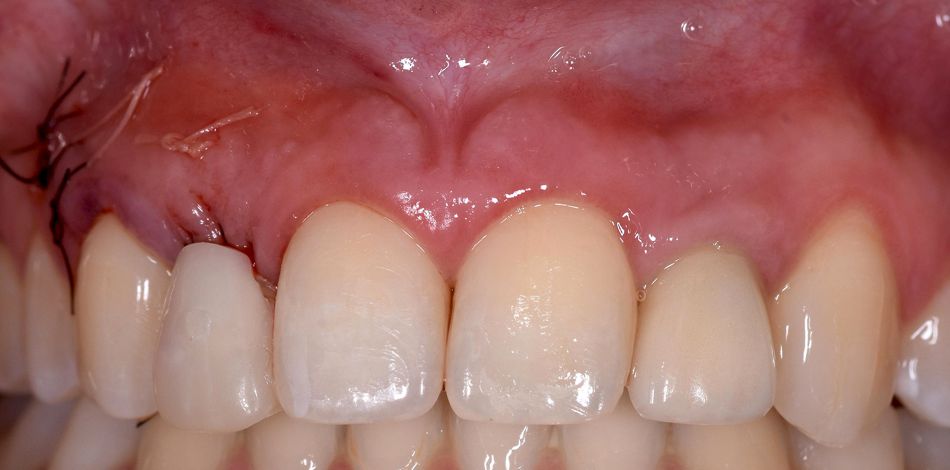

A subepithelial connective tissue graft was collected from the tuberosity and stabilized on the recipient area using a 5.0 PGA absorbable suture. (Fig. 15) A 5.0 polyamide suture was then used to close the wound. (Fig. 16-17)

A provisional acrylic Maryland tooth was bonded to the adjacent teeth for the subsequent healing period (4 months) (Fig. 18) and a final periapical radiograph was taken after surgery using a Kodak RVG 5200 sensor (Carestream®). (Fig. 19)

The first week of the healing period passed without any complications. (Fig. 20-21)